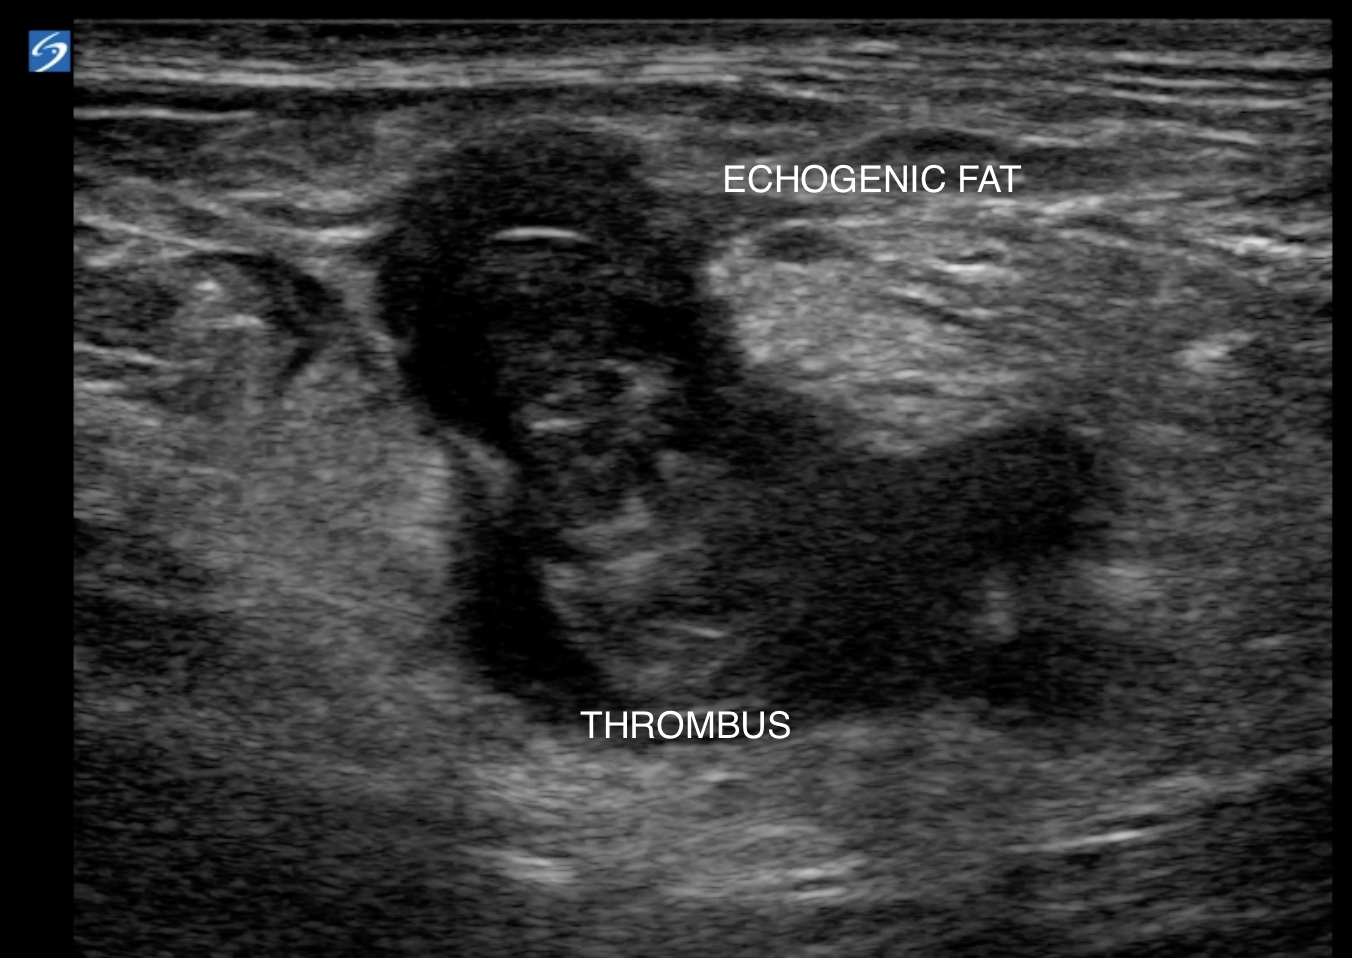

Acute thrombus in the lumen leads to inflammation and can cause the fat surrounding the vein to appear hyperechoic. This can be your first clue that something bad is going on.

Sometimes you may also see echogenic fat surrounding the thrombosed vein due to inflammation.

The fat surrounding the thrombosed vein appears more hyperechoic than normal